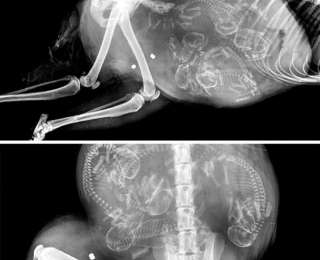

Морские свинки